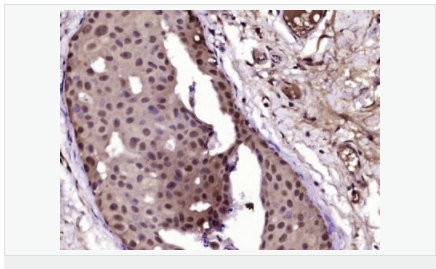

| 英文名稱 | Progesterone Receptor |

| 中文名稱 | 孕激素受體抗體 |

| 產(chǎn)品應用 | WB=1:500-2000 IHC-P=1:100-500 IHC-F=1:100-500 Flow-Cyt=1ug/Test ICC=1:100-500 IF=1:100-500 (石蠟切片需做抗原修復) not yet tested in other applications. optimal dilutions/concentrations should be determined by the end user. |

| 細胞定位 | 細胞核 細胞漿 |